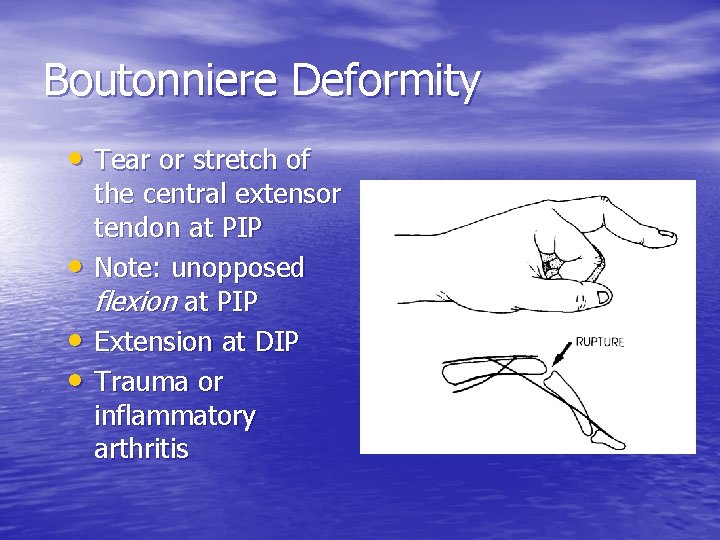

Boutonniere Deformity • Tear or stretch of • • • the central extensor tendon at PIP Note: unopposed flexion at PIP Extension at DIP Trauma or inflammatory arthritis